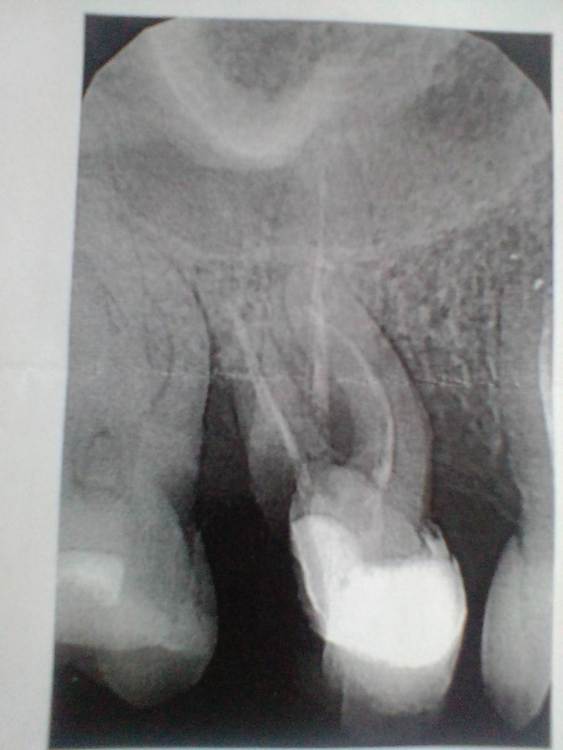

asssiriya Опубликовано 19 июня, 2023 Поделиться Опубликовано 19 июня, 2023 Можно ли сохранить зуб? Ссылка на комментарий

Notherbrick Опубликовано 19 июня, 2023 Поделиться Опубликовано 19 июня, 2023 Здравствуйте. Судя по снимку лучше удалить. 1 Ссылка на комментарий

IvanK Опубликовано 20 июня, 2023 Поделиться Опубликовано 20 июня, 2023 11 часов назад, asssiriya сказал: Можно ли сохранить зуб? Здравствуйте, нет Ссылка на комментарий

red_butler Опубликовано 20 июня, 2023 Поделиться Опубликовано 20 июня, 2023 3 часа назад, asssiriya сказал: Почему нет? Кариес корня, значительная степень разрушения. 1 Ссылка на комментарий